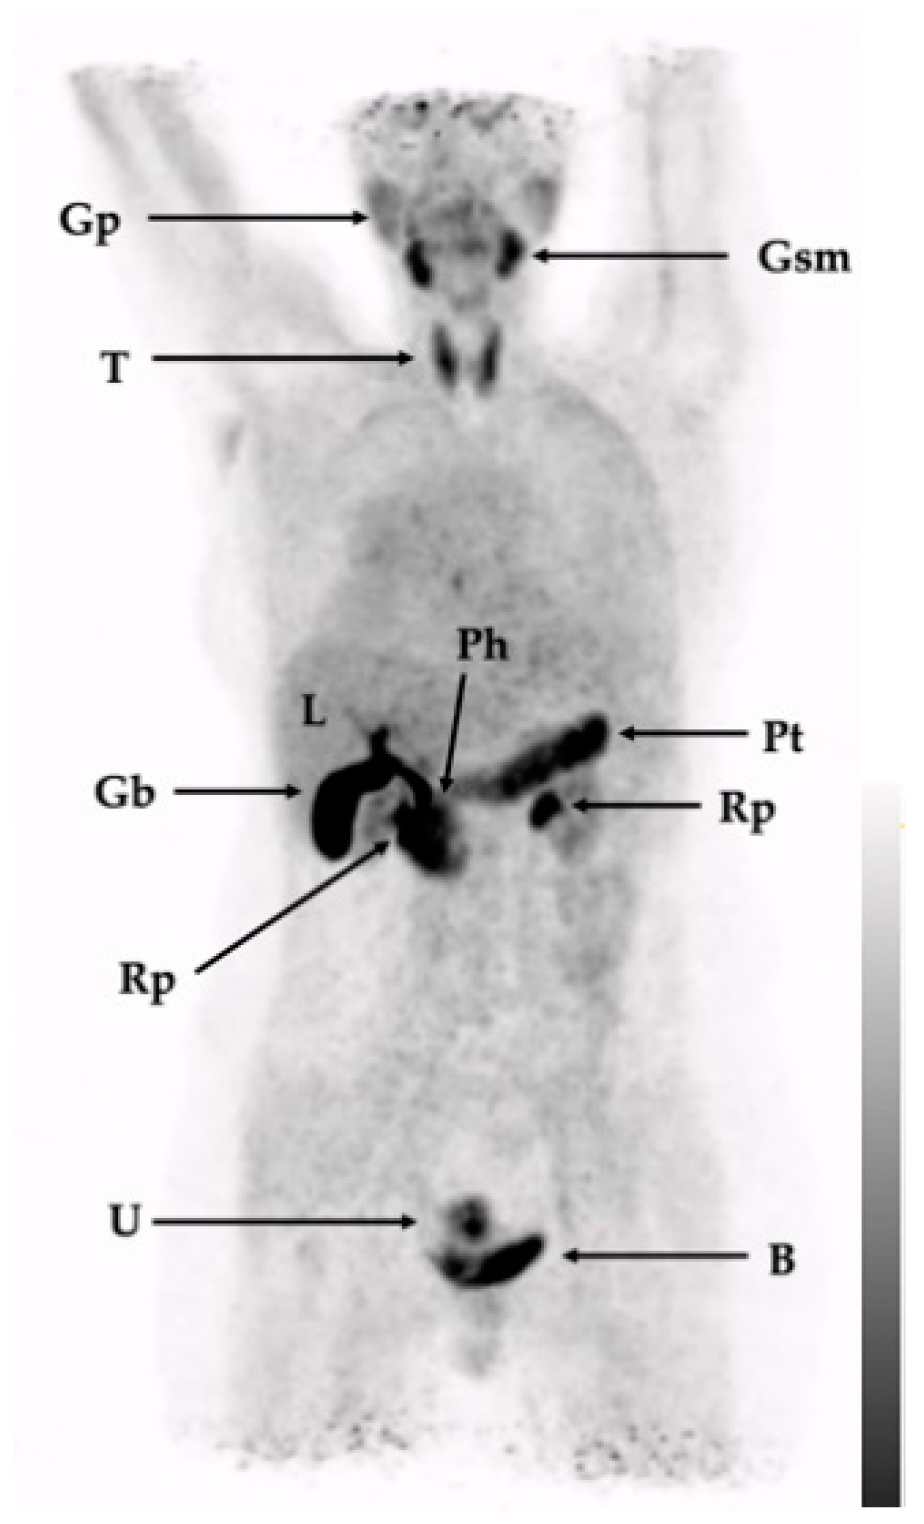

| Tissue/Organ | SUVmax [Average ± SD] | SUVmean [Average ± SD] |

|---|---|---|

| Spleen | 2.4 ± 0.5 | 1.6 ± 0.5 |

| Liver | 2.5 ± 0.4 | 1.9 ± 0.3 |

| Red marrow (vertebrae) | 2.3 ± 0.4 | 1.5 ± 0.5 |

| Kidney | 3.0 ± 1.1 | 2.4 ± 0.9 |

| Brain (frontal cortex) | 0.4 ± 0.2 | 0.1 ± 0.1 |

| Pituitary gland | 1.7 ± 0.6 | 1.0 ± 0.3 |

| Submandibular gland | 6.3 ± 1.2 | 4.3 ± 2.1 |

| Thyroid | 6.1 ± 1.8 | 3.9 ± 1.2 |

| Pancreas | 7.8 ± 2.5 | 4.5 ± 1.5 |

| Lung | 0.8 ± 0.3 | 0.6 ± 0.2 |

| Muscle (quadriceps) | 0.9 ± 0.2 | 0.6 ± 0.2 |

| Blood pool (aorta) | 1.8 ± 0.9 | 1.5 ± 0.7 |

| 1 (Figure 3) | Sarcoidosis (left cervical lymph node manifestation), in the past inflammatory pulmonary activity, the activity of the sarcoidosis during image acquisition was not clear. History of DCIS in the left breast | Lymph node extirpation, modified radical mastectomy on left side, prophylactic radical modified mastectomy on right side | Only physiological tracer distribution with no further suspect tracer accumulations |